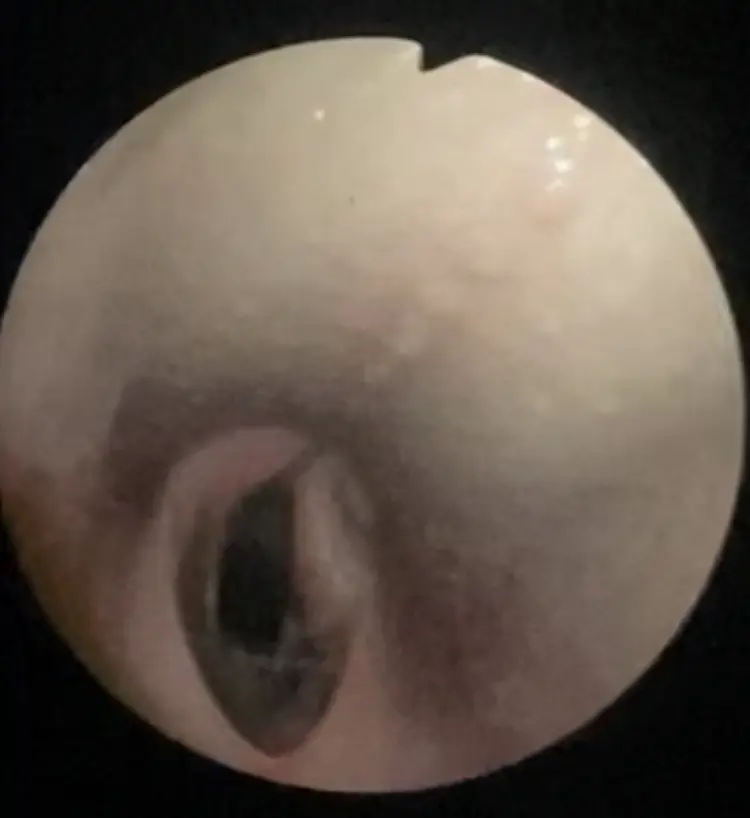

- Upper airway endoscopy to detect possible respiratory pathologies.